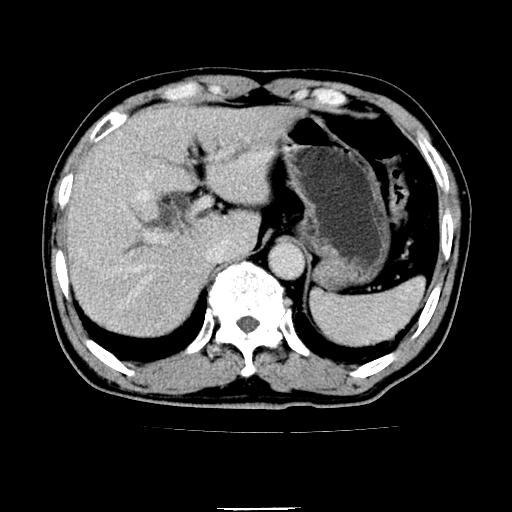

以下是引用chenqiong在2010-3-25 20:56:00的发言:[br]1、胆囊炎,胆囊息肉[br]2、肝内胆管及胆总管扩张,胆总管下端结石[br]3、十二指肠乳头旁憩室

以下是引用zxl51642在2010-3-26 10:47:00的发言:[br]胆囊炎,胆囊息肉,胆总管扩张,但未看到明显肿块,肝内胆管扩张不像恶性,炎性狭窄或阴性结石可能吧,建议mrcp,右肾小囊肿